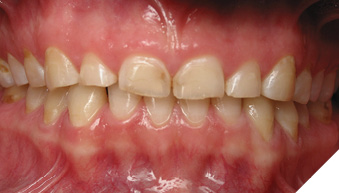

Articulated diagnostic casts showed very limited to no overjet and 90% of overbite. The wear pattern on the palatal aspect of her maxillary teeth appeared to be secondary to her tight occlusion since mandibular anterior teeth were in close contact with these surfaces with no “room” for protrusive movements. The diagnosis for this patient was: partial edentulism, failing existing restorations and attrition and abfraction secondary to parafunction. We discussed different options, including orthodontics in order to increase her overjet so we could have prosthetic space to restore her worn down teeth. We also discussed tooth replacement options. After a second consultation appointment which she attended with her husband, she decided that she did not want to replace her teeth with removable prosthetics. She also declined referral to an orthodontist. After discussion of multiple options of treatment to address all her chief complaints, her treatment consisted of a full mouth reconstruction with full coverage restorations in Zirconia for teeth 11-13,17,22-23,25-27,32-42, 44-47 and partial coverage restorations with lithium disilicate restoration for teeth 33,34 and 43. Replacement of teeth was achieved with a fixed partial denture to replace tooth 36 and a 3-unit implant supported bridge to replace teeth 24-26. In terms of occlusion, we created a more favorable occlusion with a proper anterior guidance, canine disclusion with more freedom for protrusive movements, which hopefully would decrease the parafunction, and alleviate some of her muscle pain. Before completing the case, the patient spent several weeks with provisional restorations which reflected the increase in vertical dimension of occlusion and the new occlusal scheme. During this trial phase, we assessed comfort, esthetics, function, decrease in pain and speech (Figs. 12-17).

Fig. 12

During a 6 month follow up visit, the patient presented with reduced pain in her masticatory muscles and no sensitivity on her teeth. She was also pleased that her chewing function had improved and she loved her brighter smile. She used her night guard every night. She is in a 6-month recall protocol to ensure all restorations are in proper condition and that her occlusion continues to be ideal. We also monitor the health of the soft tissues and peri-implant health.